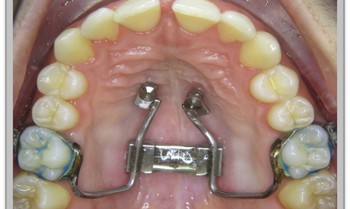

Die GNE lässt sich heutzutage auch als „Hybrid“ herstellen, bei welcher 2 Backenzähne und zwei Mini-Pins im Gaumen zur Verankerung dienen. Dies hat entschiedene Vorteile gegenüber der konventionellen GNE-Technik.

Die von der Apparatur ausgeübte Kraft wird direkt auf den Knochen übertragen und nicht erst über die Verankerungszähne sekundär auf den Knochen gelenkt. Damit reduzieren sich die Nebenwirkungen auf die Zähne auf ein Minimum.

Bei Vorhandensein aller bleibenden Zähne kommt die „Bänder-GNE“ zum Einsatz, bei Vorliegen von Milchzähnen die „Kappen-GNE“.